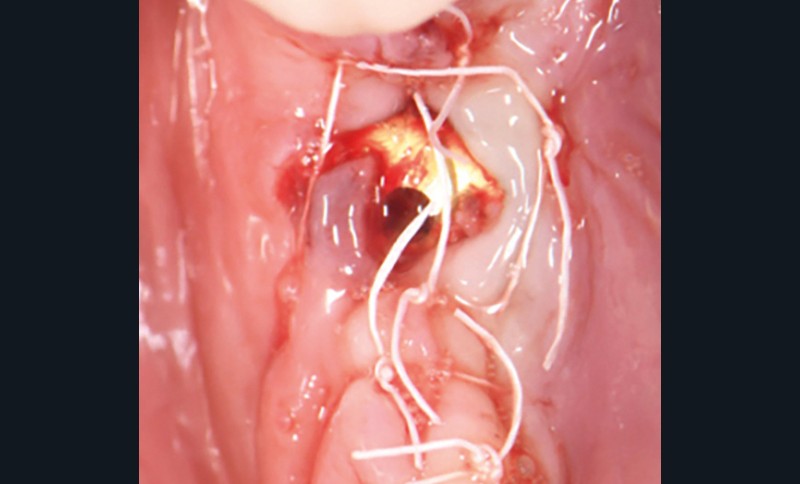

- Péri-implantite sur l’implant 47, diagnostiquée en août 2022

- Poches de 6 à 7 mm

La couronne a été déposée et une vis de couverture mise en place. La patiente a reçu un nettoyage supra-gingival général avec une attention particulière pour l’implant 47, et une irrigation locale avec du gel de chlorhexidine et du peroxyde d’hydrogène pour réduire l’inflammation des tissus. De l’amoxicilline (3 x 500 mg) a été prescrite, à commencer la veille de l’intervention chirurgicale.

En ce qui concerne le traitement de la péri-implantite, l’identification et le contrôle des facteurs de risque locaux et systémiques, ainsi que la qualité des tissus mous environnants, sont des facteurs à prendre en compte. En ce qui concerne la partie prothétique, une évaluation minutieuse de la prothèse doit être faite pour envisager si nécessaire une nouvelle conception. L’approche électrolytique exige que la prothèse sur l’implant…